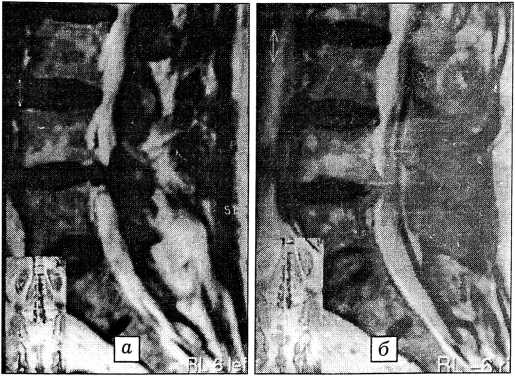

Рис. 1. Компьютерная томограмма диска L5-S1: а — до операции (протрузия 6 мм); б — через 1 мес после операции (протрузия 4 мм).

Рис. 2. Магнитно-резонансная томограмма поясничного отдела позвоночника: а — до операции (протрузия L4-5 диска 8 мм); б — через 1 мес после операции (протрузия диска 6 мм).

Четырем пациентам через 2 нед после операции было проведено повторное лучевое обследование (КТ и МРТ). У двух из них протрузия диска L4~5, составлявшая 8 и 6 мм, после операции уменьшилась на 2 мм (рис. 1 и 2). В одном случае дооперационная протрузия диска L4-5 в 4 мм была устранена полностью. У пациента со значительной дегенерацией диска L4-5 и его протрузией в 6 мм заметных изменений на КТ не выявлено, хотя клинический эффект был достаточно выраженным.